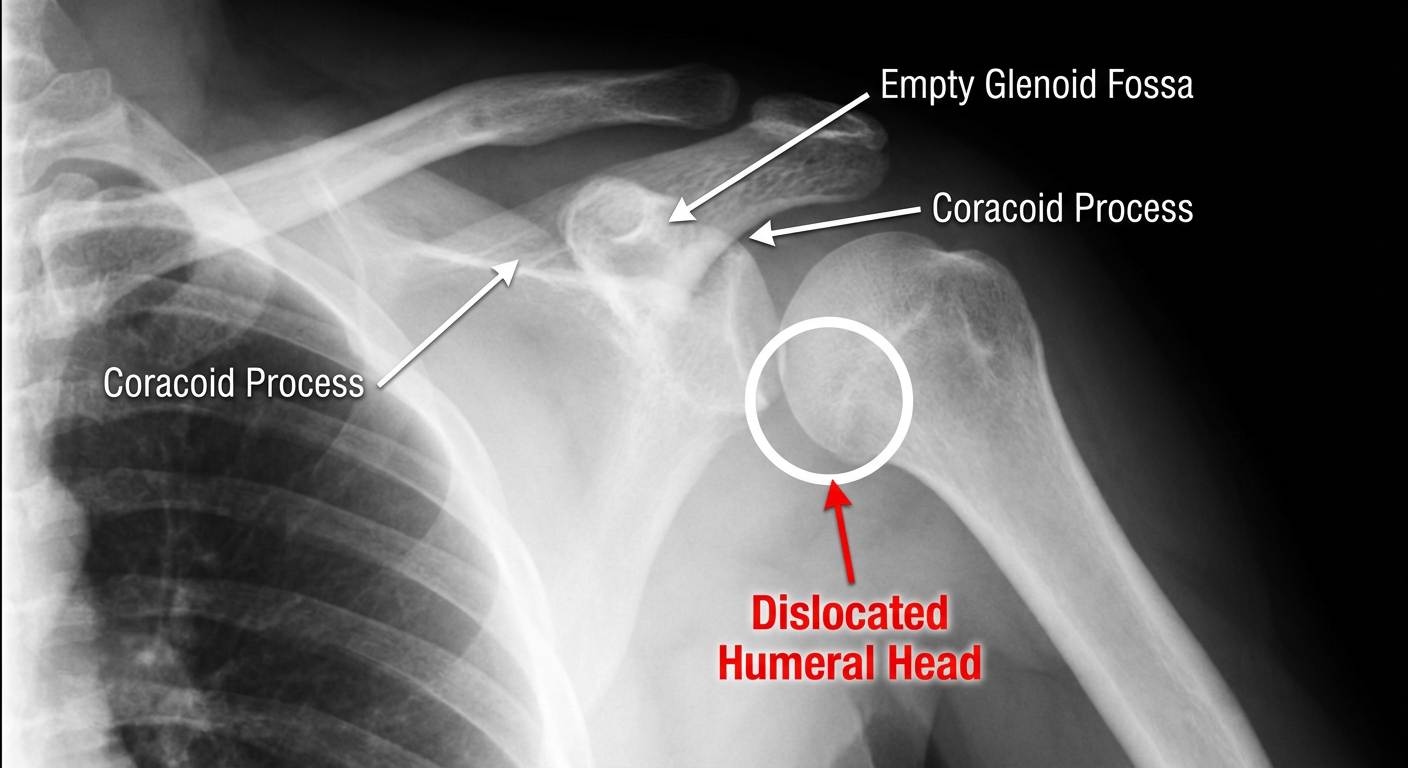

| Humeral head position | Displaced inferiorly and medially, lying beneath the coracoid process — classic subcoracoid anterior dislocation |

| Loss of joint congruity | The humeral head is no longer seated in the glenoid fossa; the normal "ball-in-socket" relationship is lost |

| Empty glenoid sign | The glenoid fossa appears vacant on the AP view |

| 🔴 Dislocated Humeral Head | The large round opacity sitting below and medial to where it should be — beneath the coracoid, where the finger is pointing |

| ⬜ Empty Glenoid Fossa | The socket area that appears vacant — no humeral head sitting in it |